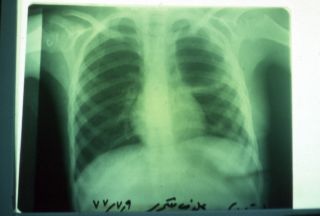

کیست هیداتیک Hydatic Cyct